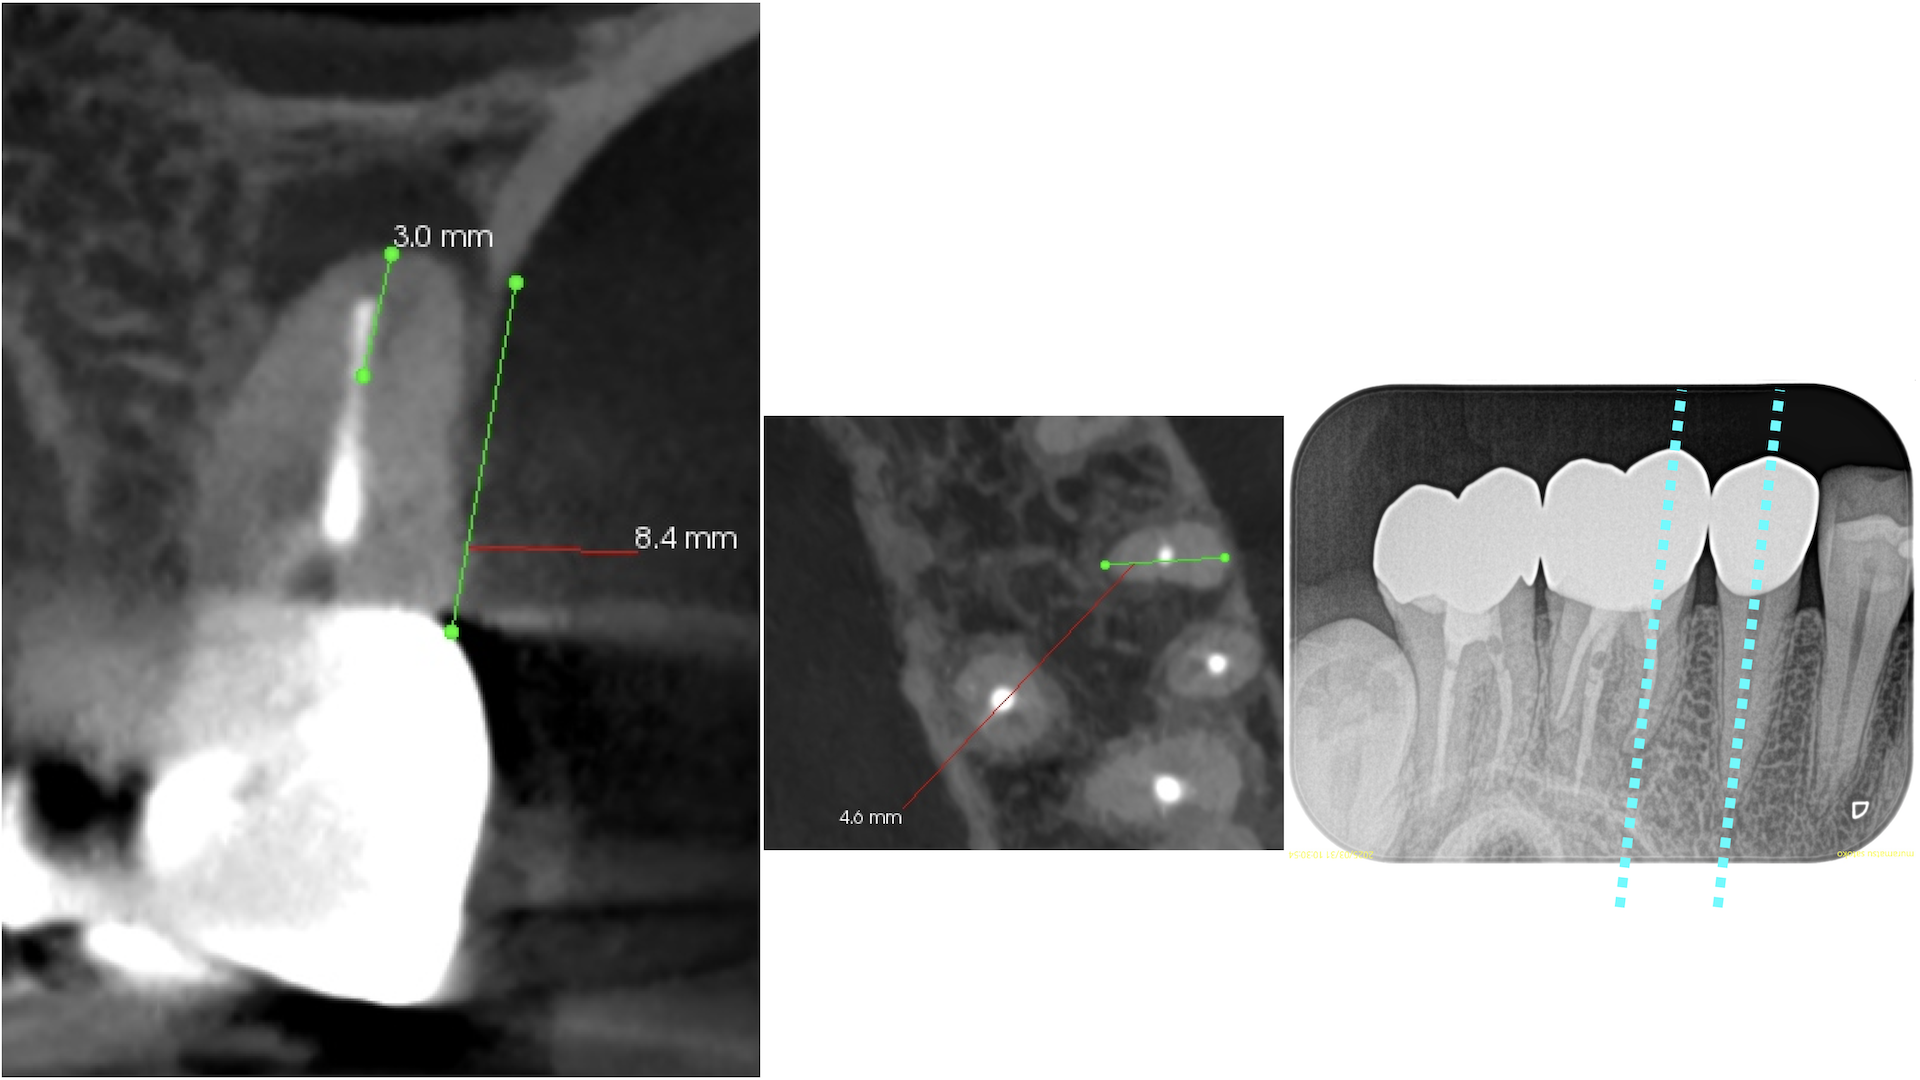

MBに大きな病変がある。DB,Pには病変はない。

これが検査での圧痛の原因だろう。

またすでに必要十分に拡大形成がなされていること,

MBの中央にGutta Percha Pointがあることから、MB2はなくMB1のみの処置でいいとわかるところもCBCTの強みである。

さておき、この問題を解決するには再根管治療でなく歯根端切除術であるということがわかる。

その際は、

クラウンのマージンより8.5mmの位置にMBのApexがあり3mm切断するには頬舌的距離が4.6mm必要で、MB2もないというまさにこの歯は奥歯だが、

事実上、上顎前歯のApicoectomy

と言える。